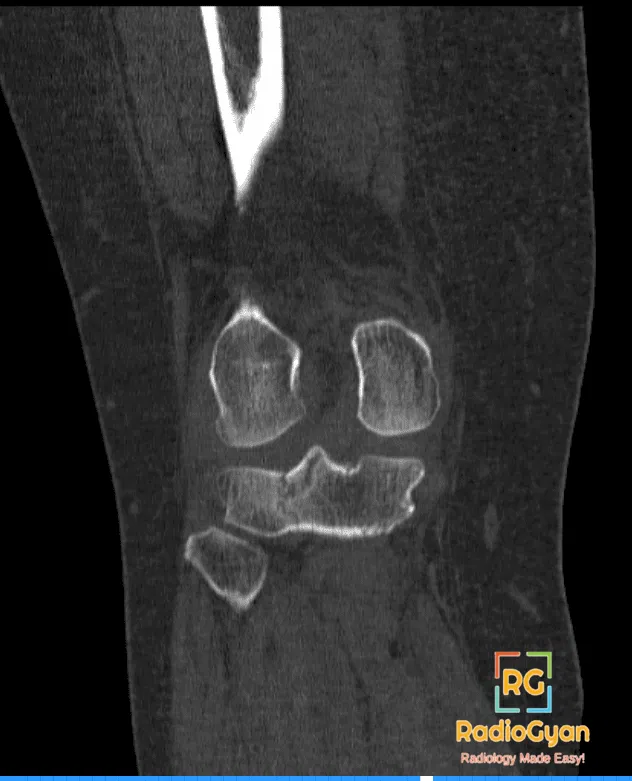

Tibial Plateau Fracture CT

Comminuted intra-articular fracture of the lateral tibial plateau with mild depression. There is an extension of the fracture into the intercondylar

notch with avulsion of the lateral tibial spine. There are a few tiny intra-articular loose bony fragments.